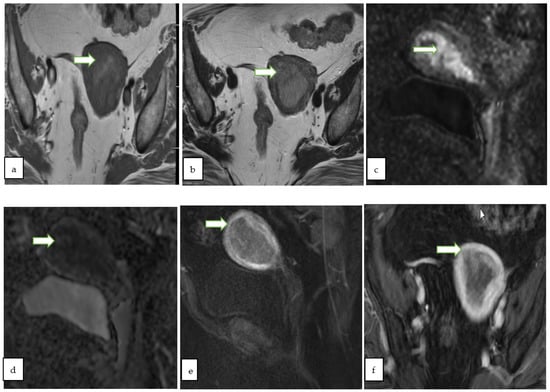

4.2. Magnetic Resonance Imaging (MRI)

- MRI is regarded as the gold standard for local delineation of most gynecological malignancies owing to superb soft tissue contrast and resolution without exposing the patients to ionizing radiations. In addition, DCE and DWI provide additional data regarding tissue perfusion and cellular density, respectively.

- Thomassin-Naggara, I.; Poncelet, E.; Jalaguier-Coudray, A.; Guerra, A.; Fournier, L.S.; Stojanovic, S.; Millet, I.; Bharwani, N.; Juhan, V.; Cunha, T.M.; et al. Ovarian-Adnexal Reporting Data System Magnetic Resonance Imaging (O-RADS MRI) Score for Risk Stratification of Sonographically Indeterminate Adnexal Masses. JAMA Netw. Open 2020, 3, e1919896. [Google Scholar] [CrossRef]

- Sadowski, E.A.; Thomassin-Naggara, I.; Rockall, A.; Maturen, K.E.; Forstner, R.; Jha, P.; Nougaret, S.; Siegelman, E.S.; Reinhold, C. O-RADS MRI Risk Stratification System: Guide for Assessing Adnexal Lesions from the ACR O-RADS Committee. Radiology 2022, 303, 204371. [Google Scholar] [CrossRef]